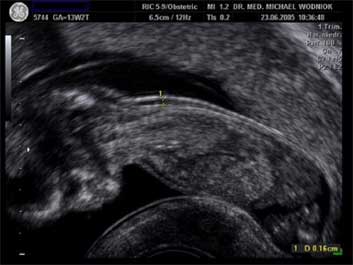

Die Nackenfalte stellt sich im Ultraschallbild im Bereich des hinteren Halses als ein dunkles Areal dar, welches auch bei fast allen gesunden Kindern in einer bestimmten Dicke (1-2 mm) zu sehen ist. Diese Nackenfalte ist normalerweise nur in der 11. bis 14. SSW darstellbar und verschwindet im weiteren Verlauf der Schwangerschaft.